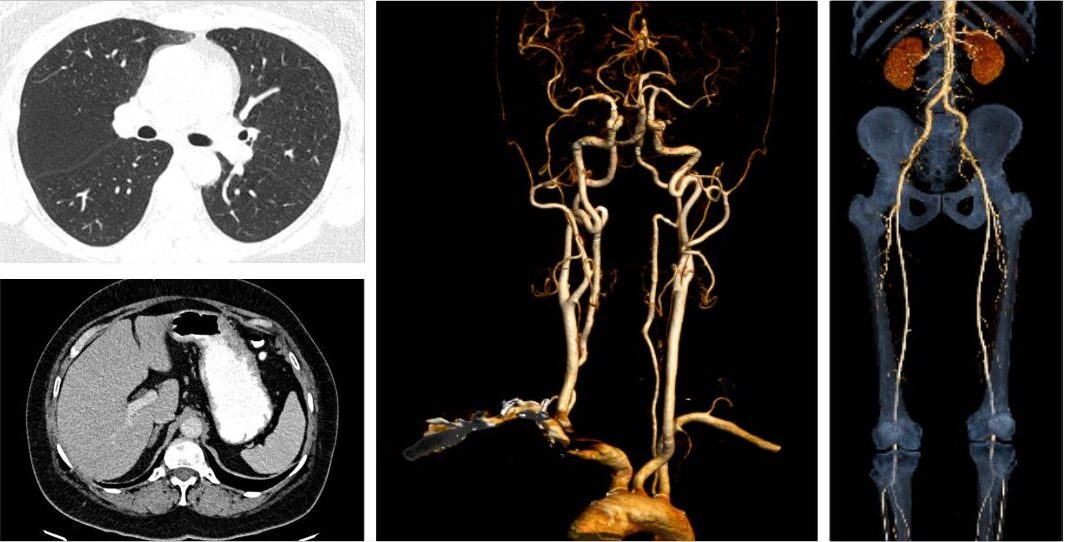

CT coronary angiography is a non-invasive imaging test that, through the use of advanced computed tomography technology and contrast dye, provides highly-detailed three-dimensional images of the coronary arteries. This, in turn, allows doctors to take a close look at plaque buildup, narrowing, blockages, and the overall health of blood vessels supplying the heart.

3. Provides a Complete 360° View of the Coronary Arteries

CTCA produces:

• High-resolution 3D reconstructed images

• Cross-sectional views of the arteries

• Detailed visualization of vessel anatomy

This helps cardiologists understand:

• The location of plaques

• Composition-soft or calcified

• Degree of stenosis

• Risk of future cardiac events

Such detail is not always available with conventional angiography.